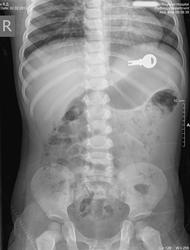

[15.10.2013] Родители проморгали

как говорится, no comments.

Сам выйдет?

Что то гложут меня тайные сомнения...на сей счет...

вот и у меня сомнения, что выйдет. ребенок больно мелкий. Если ФГДС - то нужна специальная педиатрическая аппаратура. взрослая трубка не пролезет скорее всего.

Выйдет, во всяком случае до прямой кишки дойдет, а там уже проще. Проволочные "ежи" выходят за "милый мой", правда, у взрослых. Если у эндоскопистов или хирургов не чешутся руки.

Уважаемый коллега Special.K, ! На Вашем снимке есть дата 02.02.2012. Это дата рождения?  А мы при снимках на предмет поиска инородных тел детишек раздеваем. Смущает, что тень ключика выходит за пределы тени раздутого желудка. Хотелось бы знать время предполагаемого попадания инородного тела.

Уважаемый доктор Ильич!  это дата рождения.   ребенка раздели наполовину. соглашусь, в идеале надо раздевать полностью.

Время попадания инородного тела - за 3 часа до исследования.

продолжения не будет.  скорее всего его направили в детскую областную.